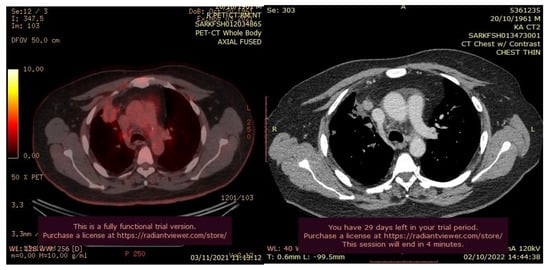

In July 2021, a 60-year-old patient came to our Cryosurgery unit, provided with a CT scan of the chest dated April 2021. The CT scan revealed the presence of a hyper-metabolic lesion with a size of 2.8 cm and involving the right upper/middle lobe related to the neoplastic process. The presence of hypermetabolic lytic bone lesions involving the right proximal femur T-10 and the left transverse process of T-9 was also confirmed, highlighting bone metastasis (Figure 4).

Figure 4. CT scan (left) and Pet- CT (right) images from April 2021 with evidence of bone metastases. The arrows indicate the tumor’s location.